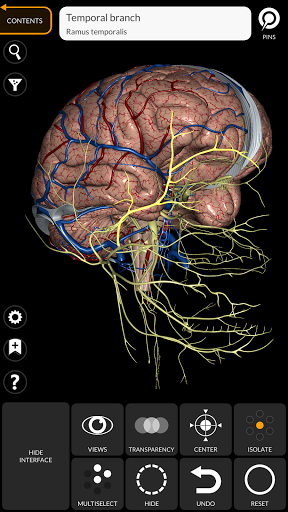

"Anatomy 3D Atlas" дозволяє легко та інтерактивно вивчати анатомію людини.

Завдяки простому та інтуїтивно зрозумілому інтерфейсу можна спостерігати кожну анатомічну структуру під будь-яким кутом.

Анатомічні 3D-моделі особливо деталізовані та мають текстури з роздільною здатністю до 4k.

• Нервова система

• Можливість приховування або ізоляції однієї чи кількох вибраних моделей

• Функція прозорості

• Вибравши модель або шпильку, з’явиться відповідний анатомічний термін